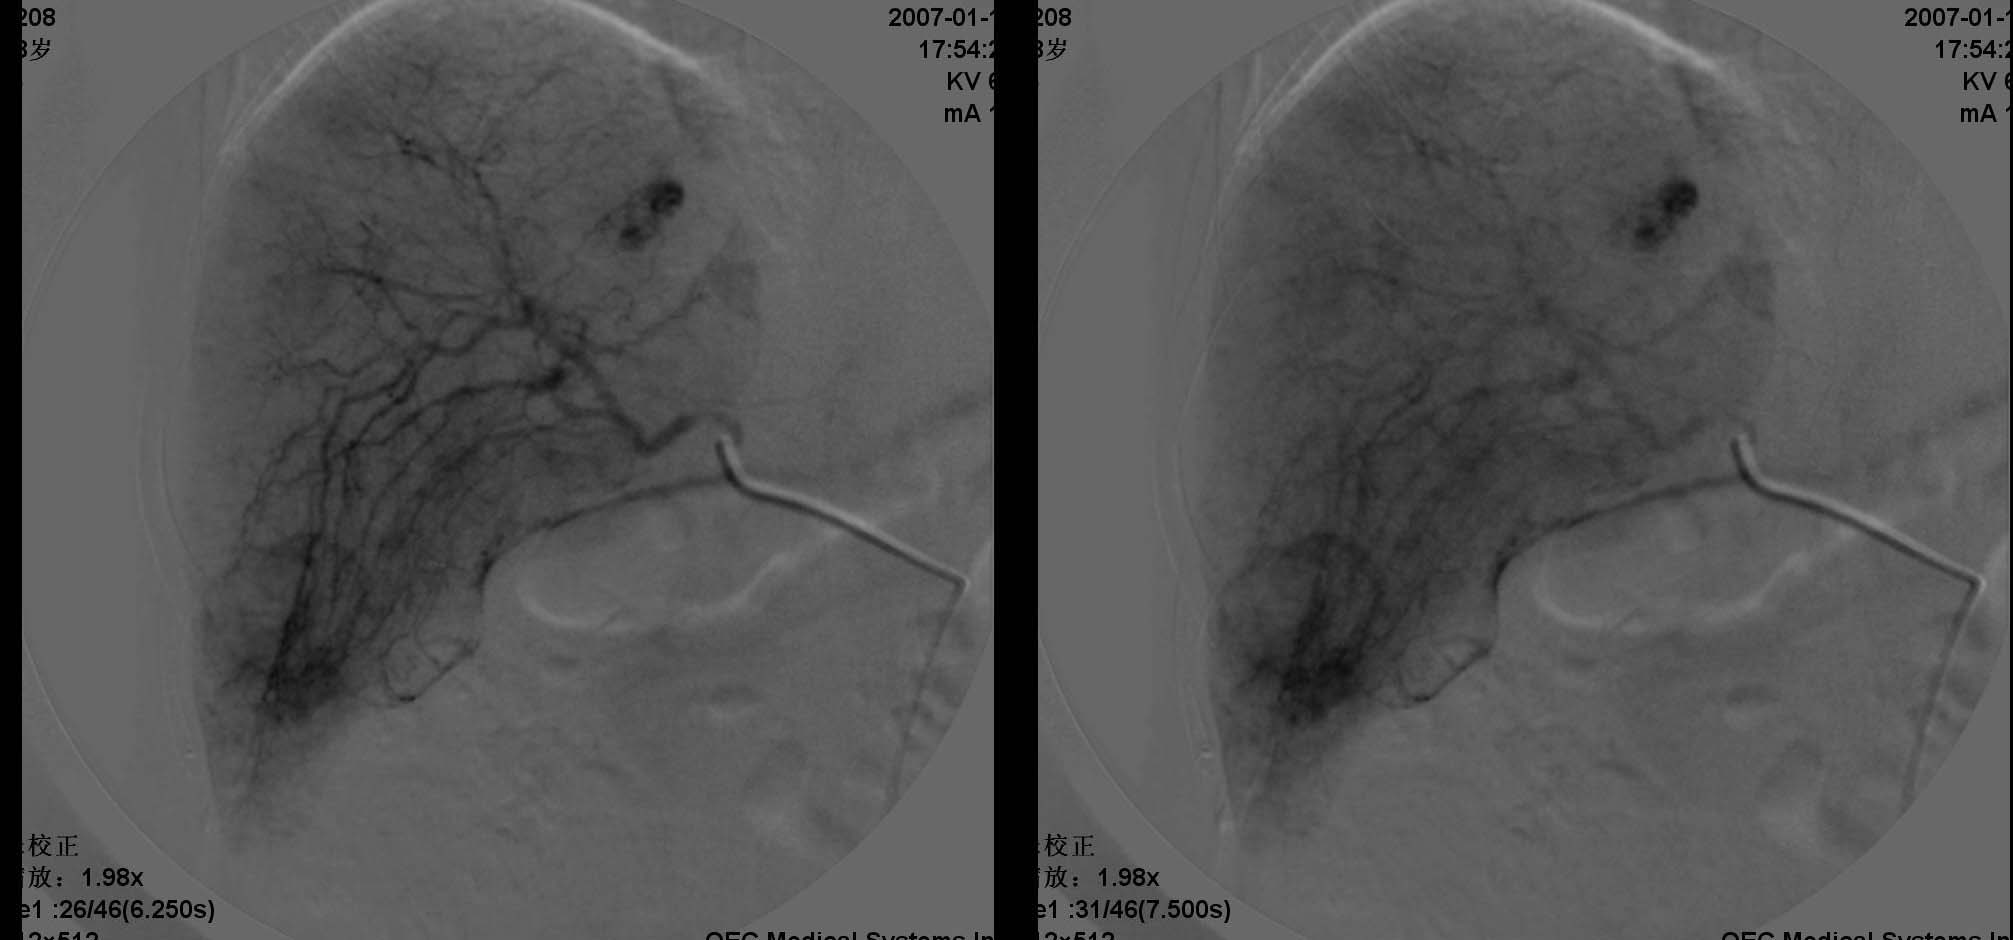

肝转移瘤的表现多种多样,血供丰富的肝转移瘤常呈现与肝细胞癌相似的表现,肝动脉增粗、扭曲,分支血管增多、紊乱呈网状,血管僵硬、受压移位等.巨块型转移灶实质期肿瘤染色还可见到较明显的中心性坏死所显示的中央低密度区。少血供者,肿瘤血管常较稀少、纤细、僵直或包绕,实质期肿瘤染色淡薄或不显影,而在肝实质染色衬托下形成低密度充盈缺损区。中血供之表现介于上述两者之间。在门静脉期,无论是多、中、少血供肝转移瘤,均显示与转移灶在动脉晚期和实质期类似的肿瘤染色。

肝转移瘤与原发性肝癌的血管造影表现在有些方面相似。在原发性肝癌中,动静脉瘘及门静脉癌栓的发生率是比较高的。肝转移瘤中少血供者占大部分,血管表现为纤细、稀少、僵硬,肿瘤染色较浅;而在原发性肝癌中,血管表现多为增粗、扩张、扭曲,分支血管增多、紊乱等。

肝内多发肿块是肝转移瘤的特征,而原发性肝癌一般常为单发或仅出现少量病灶。右叶多发少血供占位病变可首先考虑转移瘤。

五、血管瘤

血管瘤的dsa诊断与ct诊断同一理论,但通常出现“枝头挂果征”象或“腊梅征象”,征象出现一般见于较大血管瘤,较大血管瘤也可出现动静脉短路(avs),此例血管瘤较小,“枝头挂果征”不明显。